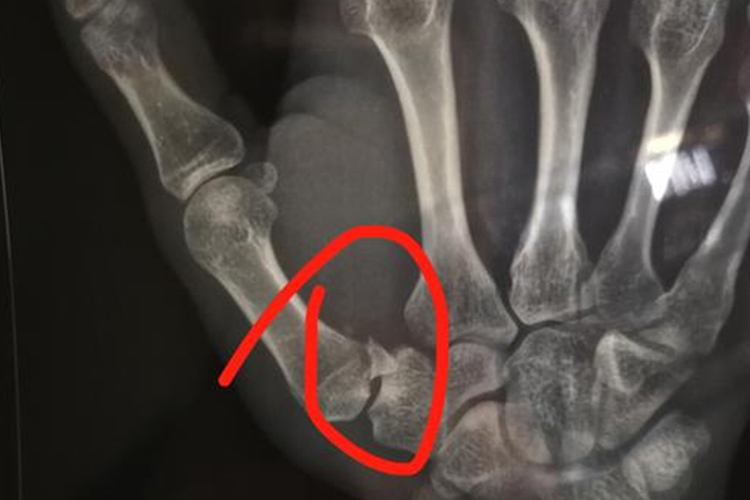

手部骨折:如第1掌骨骨折,临床表现为第1掌骨基底处疼痛、肿胀、畸形、拇指位于内收位,拇外展、内收、对掌动作受限。正位X线及侧位 X线片可显示骨折及脱位情形。